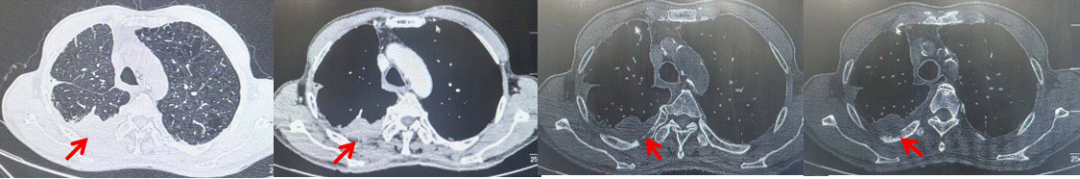

2024.11.19患者出现右侧胸痛,复查胸部CT检查示右侧胸膜肿物,大小约31mmX24mm,右侧4、5肋骨骨质破坏,考虑转移(如图2)。建议患者穿刺活检取病理明确诊断,患者拒绝,经MDT会诊后结合影像学表现及病史考虑为胸膜转移,肋骨转移,分期为rT0N0M1a IVA期,DFS仅仅17个月。2024.12.05起行信迪利单抗联合培美曲塞+卡铂方案治疗4周期,复查胸CT评效PR(如图3)。之后给予信迪利单抗+培美曲塞维持治疗6周期,期间复查CT评效PR(如图3)。目前信迪利单抗+培美曲塞维持治疗中,截止至目前PFS约为8个月,治疗期间未出现明显毒副反应。

图3:患者免疫联合化疗治疗后胸部CT,(A、B)图展示信迪利单抗联合培美曲塞+卡铂治疗

4周期(2025.02)疗效,(C、D)图展示信迪利单抗+培美曲塞维持治疗6周期(2025.07)疗效

2024.09.12复查胸部CT示左侧胸膜结节,大者约为27mmx13mm,考虑转移可能性大,纵隔淋巴结增大,恶性?(如图6)。患者行胸膜穿刺活检取病理,结果示(胸膜)结合免疫组化,支持鳞状细胞癌,PD-L1(克隆号28-8)TPS约20%。分期为rT0N2bM1a IVA期,DFS为10个月。2024.09.24起行替雷利珠单抗联合紫杉醇+卡铂方案治疗4周期,复查胸CT评效SD(如图7)。后患者因脑梗塞停止治疗,于综合医院就诊,后未返院复查及治疗。

图7:替雷利珠单抗联合白蛋白紫杉醇+卡铂治疗4周期后(2024.12)胸部CT肺窗及纵隔窗